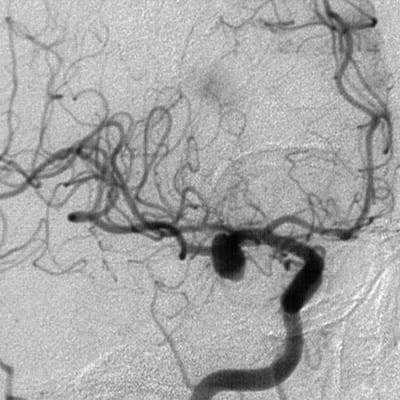

Если после проведения МРТ или КТ у врача остаются сомнения в диагнозе, если у данной аневризмы достаточно сложная форма либо очень небольшие размеры, большим подспорьем может стать дигитальная субтракционная ангиография (ДСА). Дигитальная - значит «цифровая». Субтракционная означает, что при исследовании исключаются изображения скелета, мягких тканей, видны только сосуды. Причём современная методика позволяет получать изображение в формате 2D (двухмерном) и 3D (трёхмерном) и даже вращать картинку, что даёт возможность уточнить локализацию аневризмы и оценить её расположение по отношению к магистральным сосудам головного мозга. Это помогает доктору понять, нужна ли операция в данном случае, и если да, то выбрать вид оперативного вмешательства и доступ к аневризме. Позже ДСА позволяет наблюдать за аневризмой (в том числе и после операции).

- Ангиографию. Церебральная ангиография позволяет установить расположение, форму и размеры аневризмы. В отличие от рентгенологической ангиографии магнитно-резонансная (МРА) не требует введения контрастных веществ и может проводиться даже в остром периоде разрыва аневризмы сосудов головного мозга. Она дает двухмерное изображение поперечного сечения сосудов или их объемное трехмерное изображение.

КТ-ангиография головного мозга (3D-реконструкция). Аневризматическое расширение левой средней мозговой артерии